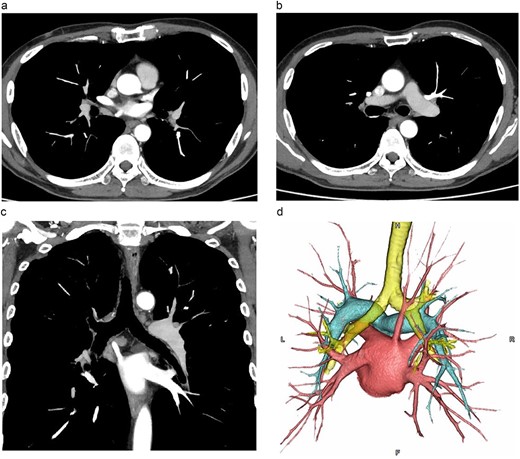

The patient was a 60-y-old man diagnosed as having squamous cell carcinoma measuring approximately 40 mm in the middle thoracic esophagus (Mt). The CT scan showed an anomalous vessel 7.8 mm in diameter arising from the right upper lobe, running posterior to the right bronchial tree, and emptying directly into the LA (Fig. 1a–c), which was correctly identified as a RTPV.

CT images. (a, b: axial images, c: coronal image, d: 3D image). The vessel was observed arising from the PVs draining the posterior upper lobe, running posterior to the RMB, and draining into the LA.